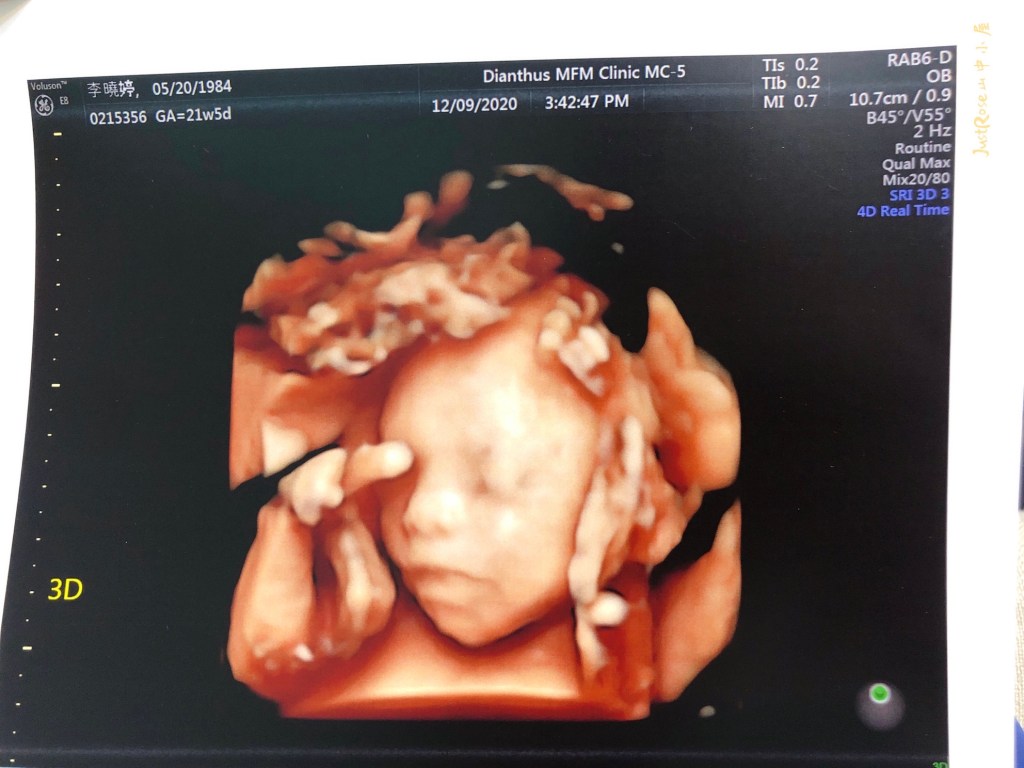

藍天,親愛的,這是你剛開始照超音波,正常俊俏的臉阿

兒阿~ 有這麼痛苦嗎?

被超音波技術員阿姨擠壓了1個小時,但,這臉部表情也太…

臉皺成這樣,大家都說像個老頭了~

做超音波的前一天,跟藍天溝通了明天會花很多時間照超音波,但是我沒想到對寶寶來說,是一直被擠壓,是被打擾的。一開始很配合,還有在活動,最後技術阿姨要數藍天的右手指時,他的手剛好握拳放在臉上,讓阿姨不容易數手指,機器只好壓來壓去、轉來轉去的看,他真的不喜歡,臉臉一直被擠壓的感覺阿。一臉告訴我們他的不喜歡~